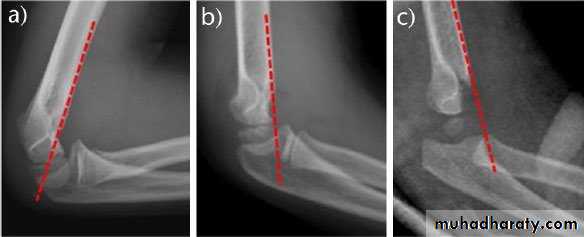

On lateral view of the elbow, there are four radiological features should be looked forAnterior humeral line :It is a line drawn down along the front of the humerus on the lateral view and it should pass through the middle third of the capitulum of the humerus. If it passes through the anterior anterior third of the capitulum, it indicates the posterior displacement of distal fragment.